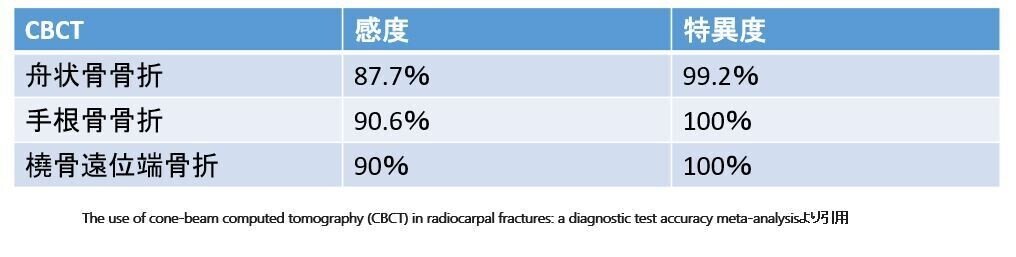

EmmaらのCBCTを用いた報告では

CBCTが舟状骨骨折に対し

感度87.7%、特異度99.2%とされています

こちらも同一文献に報告されていたので

他の手根骨骨折の場合

感度90.6%,特異度100%

橈骨遠位端骨折の場合

感度90%、特異度は100%